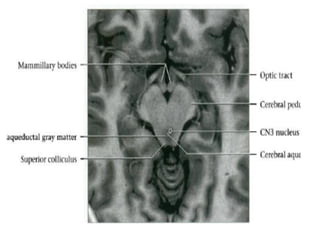

•  Midbrain

•  Ventral: Cerebral peduncles (crus cerebri) containing

corticospinal, corticobulbar and corticopontine tracts

•  Dorsal tegmentum: Ventral to cerebral aqueduct

Gray matter: Substantia nigra and red nucleus

Upper midbrain: Contains CN3 nucleus, at superior

colliculus level

Lower midbrain: Contains CN4 nucleus, at inferior

Tectum (quadrigeminal plate): Dorsal to cerebral aqueduct

• Superior & inferior colliculi

• Periaqueductal gray matter